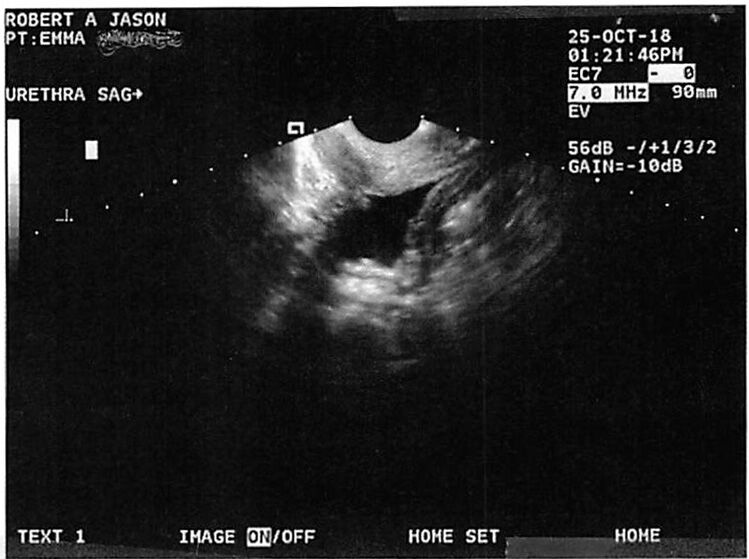

Before and after ultrasound images of the

urethral muscular tube show a remarkable transformation—from a dilated to a rejuvenated, tightened structure—demonstrating the proven effectiveness of

ThermiVa® in treating

Urinary Stress Incontinence (USI).

This improvement results from

targeted radiofrequency energy that strengthens and contracts the tissues surrounding the urethra, leading to

better closure, control, and continence—all without surgery.